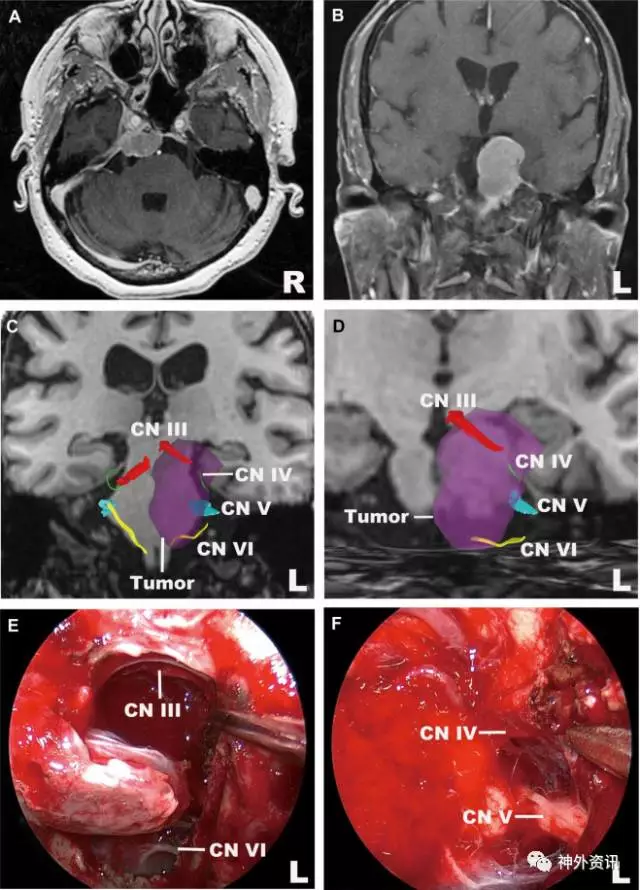

图11. 岩斜区脑膜瘤。A. MRI轴向位;B. MRI冠状位;C.动眼神经、滑车神经、三叉神经和外展神经(冠状位),以及动眼神经和外展神经与肿瘤的毗邻关系;D.左侧动眼神经和外展神经放大图(冠状位);E、F.术中图像显示,纤维束重建图与术中所见一致。